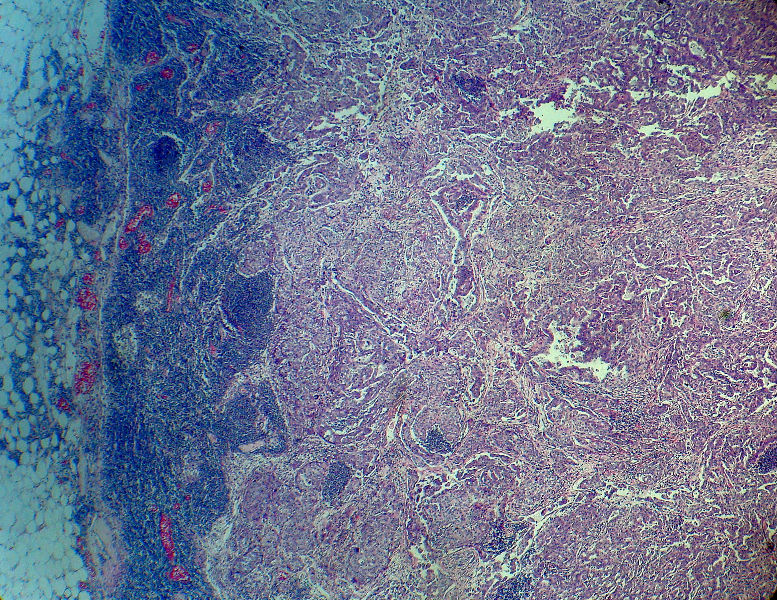

男,82岁,小肠穿孔紧急手术。

大体,小肠一段,长约60厘米,与粘膜面可见三个溃疡型肿物,肠系膜淋巴结肿大。

肿瘤呈巢片状分布,细胞大小相对一致,胞浆丰富,胞核呈细颗粒状,可见小核仁,血管较丰富,考虑神经内分泌肿瘤,加做免疫组化(Ki67、Syn、NSE、CgA、CD56)分级。

肠系膜淋巴结